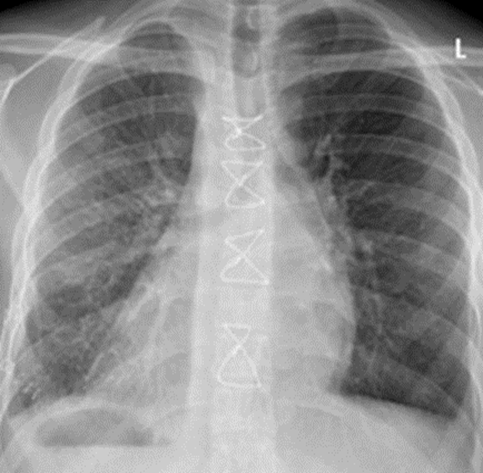

Figure 4: Postoperative X-ray after successful treatment.

The patient recovered quickly and was extubated within four hours after the procedure. In the short term after the procedure, the chambered pleural effusion on the right side closed, resulting in mediastinal displacement. With Computer tomography (CT) radiological evidence of pleural empyema, emergency right-sided empyema evacuation with decortication and adhesiolysis was performed (Figure 4).

Subsequently, evacuation of a left-sided empyema was carried out using thoracoscopic technique. The postoperative course was uneventful, and the patient was discharged in stable condition with plans for continued outpatient care.